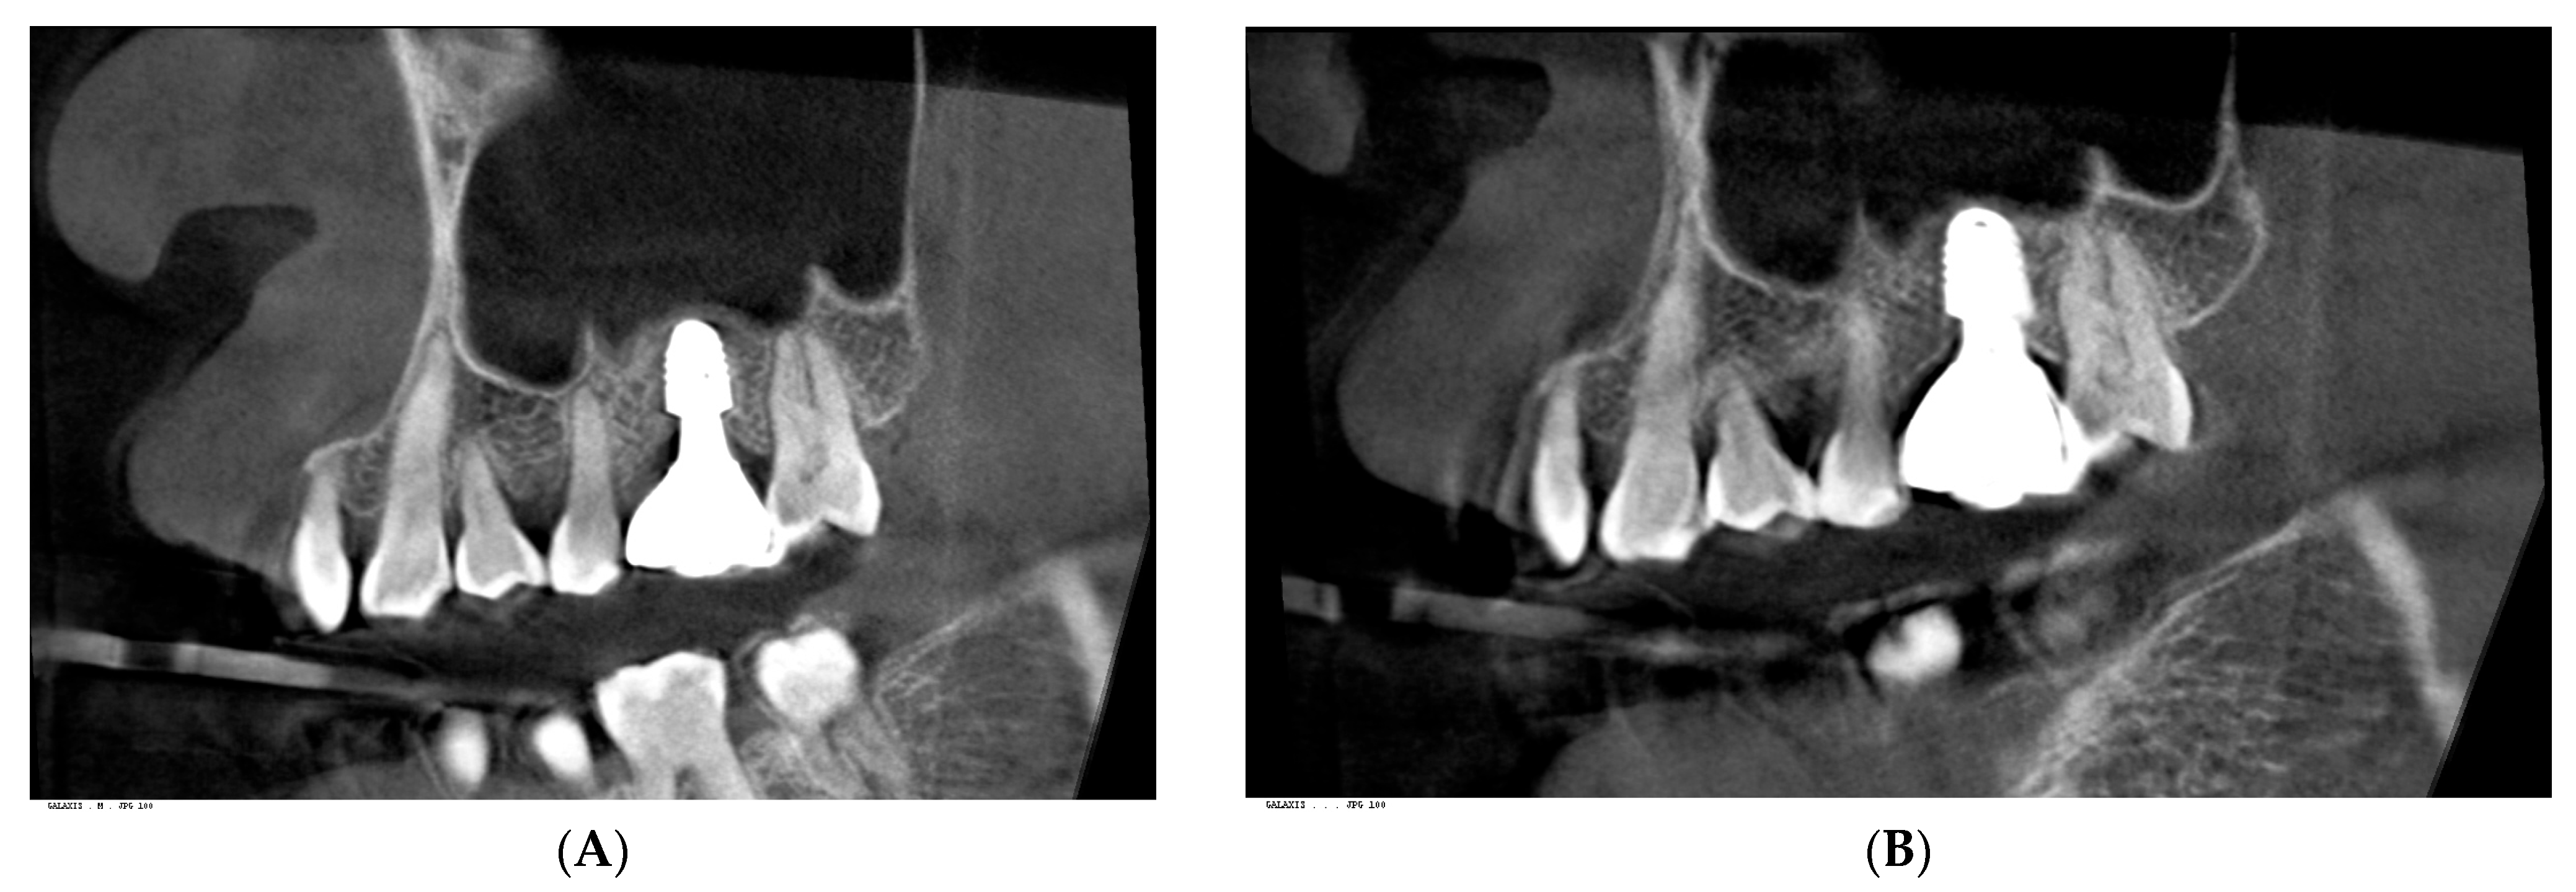

3. Radiographic and Clinical Findings

| Site | Change in cCRD (mm) | Change in pCRD (mm) | Probing Depth | BOP | Redness | Swelling |

|---|---|---|---|---|---|---|

| Lower right first molar (control) | –0.08 | –0.10 | <1 mm | No | No | No |

| Upper left first molar (treated) | –0.93 | –1.09 | <1 mm (post-treatment) | No | No | No |